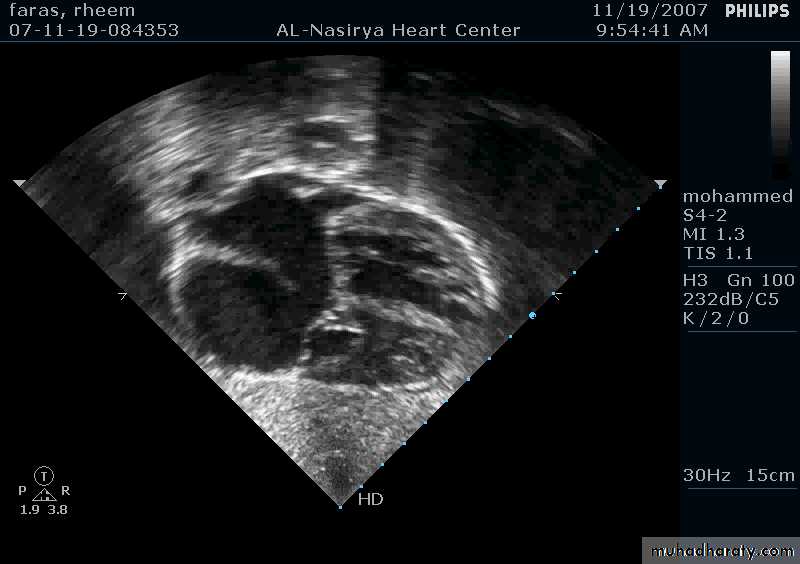

33Echocardiography & TEE

Shows the size of the defectThe direction of blood flow

The pulmonary artery pressure34

Ostium Secundum ASD

35

36